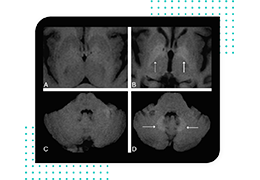

ART-Plan™ Artificial Intelligence Contouring